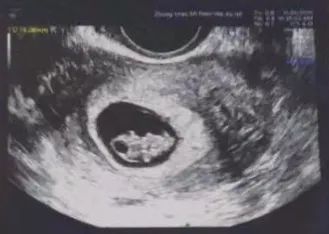

2024年12月,经过王燕医生综合评估符合移植的条件,顺利胚胎移植,一次成功妊娠!

可喜可贺,在徐士儒主任和王燕医生的帮助下,所有的努力终于有了收获!